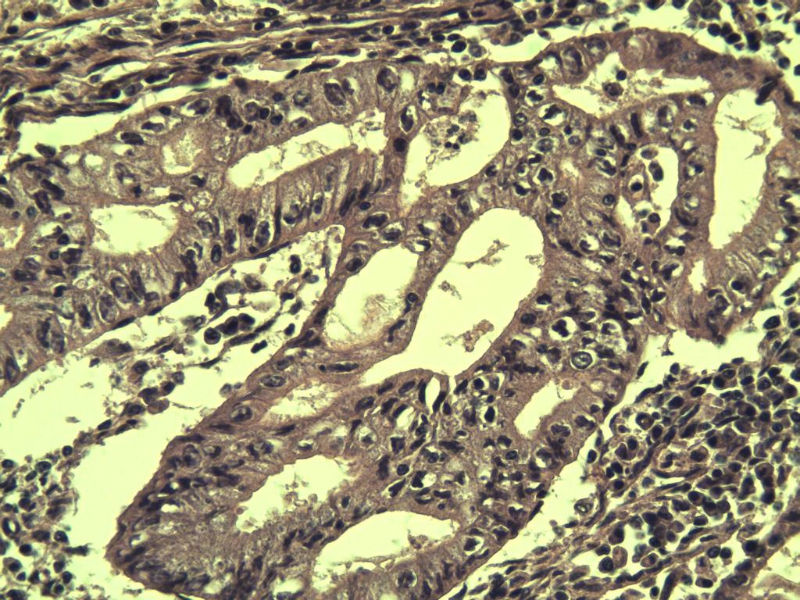

女,57岁,全切子宫一个,宫体体积 9 × 8 × 7 cm3,肌壁厚 2.5 cm,内膜菲薄,部分区域增厚达 0.4 cm(约3*2.5cm区域)。 请问各位老师  这个可以诊断子宫内膜癌了吧?      深肌层没有看到浸润。

患者因"发现下腹部包块1月多"入院  宫体体积 9 × 8 × 7 cm3,肌壁厚 2.5 cm,内膜菲薄,部分区域厚 0.4 cm(约3*2.5cm)。宫颈结构不清,长约 2.5 cm,表面欠光滑。临床诊断宫颈宫腔积液.

宫内膜样腺癌

筛状、迷路样结构

间质消失或者纤维性间质

子宫内膜样腺癌

高分化子宫内膜样癌。浸润浅肌层(深度<1/3肌层)。根据FIGO2009分期,子宫内膜癌局限于内膜层和<1/2肌层,都属于IA期。二者处理不再区别对待。